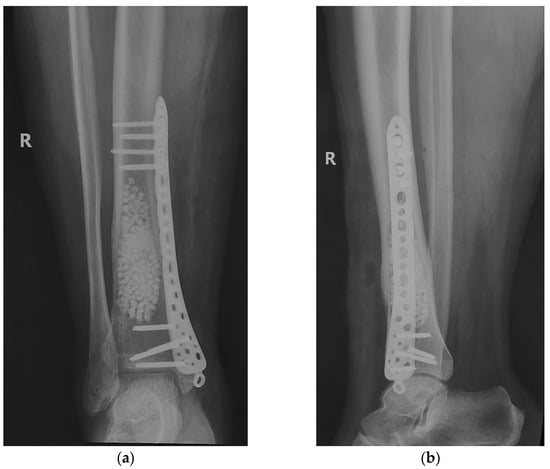

After establishing the diagnosis, the surgical treatment was initiated. We performed block resection of the extraosseous tumor formation followed by the curettage of the intradiaphyseal lesion, with the removal of the tumor tissue to the level of healthy bone tissue. The curettage process was verified by intraoperative radiology images (C-Arm mobile radiology). Tumor tissue samples were taken for histopathological examination, both from the extraosseous tumor and from the intradiaphyseal tissue, with the result being similar—RD bone lesion. After curettage, we washed the remaining bone cavity with 70% ethyl alcohol to destroy any remaining tumor cells. In order to fill the defect, bone grafting was practiced using tricalcium phosphate bone substitute (β-TCP) 25%/75% hydroxyapatite, irregular granules 3–4 mm in diameter, using about 60 cc.

As bone strength was diminished by tumor erosion of the cortex, there was a risk of fracture. Thus, safety osteosynthesis, using one plate (titanium alloy) with locked screws was associated (Figure 10).

The subsequent evolution was favorable, 6 months after the surgery the patient no longer having local pain. The radiological examination showed a favorable local evolution, without signs of tumor recurrence (Figure 12). Furthermore, the patient did not show any other specific symptoms of RDD, which is why no systemic treatment (glucocorticoids or other immunomodulatory drugs) was initiated.

Figure 10. Curettage, bone substitute grafting and plate osteosynthesis. After surgery radiographs (a) Radiological, coronal view; (b) Radiological, lateral view.

Figure 12. Radiological 6-month follow-up: (a) coronal view; (b) lateral view.